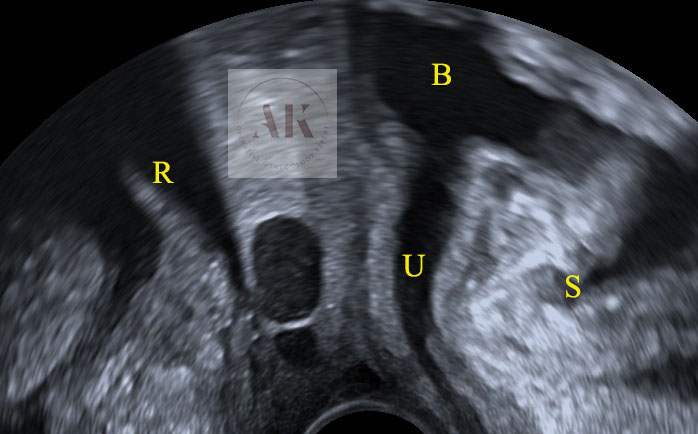

An 80-year-old female patient presents with persisting overactive bladder symptoms. After careful ultrasound examination, a unilocular cystic mass with a single urethral connecting tract containing a calculus was identified as an urethral diverticulum.

The clinician’s suspicion after acquiring a thorough patient’s history should lead to a targetted ultrasound examination combined with digital compression for possible excretion of fluid. The diagnostics may be completed with cystourethroscopy, micturating cystourethrogram, or MRI.

L (distal) / N (1)/ S (1cm) / C (single) / C (distal) / C (overactive bladder)